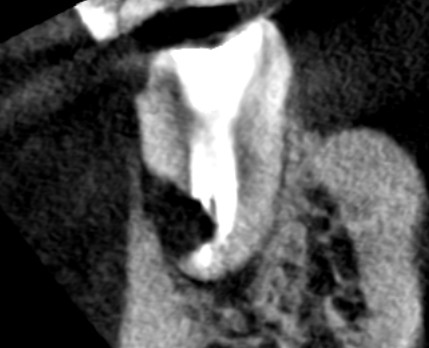

初診時の下顎第一大臼歯の矢状断のCT画像です。近心根と遠心根の根の先に膿の影がみられます。

矢印の先に膿の影がそれぞれみられますが、特に赤い矢印の先の遠心根の影が大きく、手術で根の先を半分切り残しているように見えます。